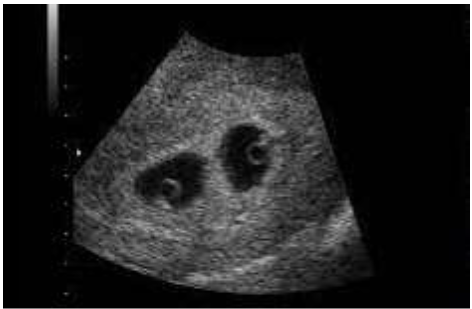

Paciente com 32 semanas de idade gestacional foi encaminhada para realização de ultrassonografia obstétrica, onde aparentemente observa-se uma placenta, dois fetos e duas cavidades amnióticas. Ela realizou um exame de ultrassom com 7 semanas de gestação em consultório, porém só possui as imagens.